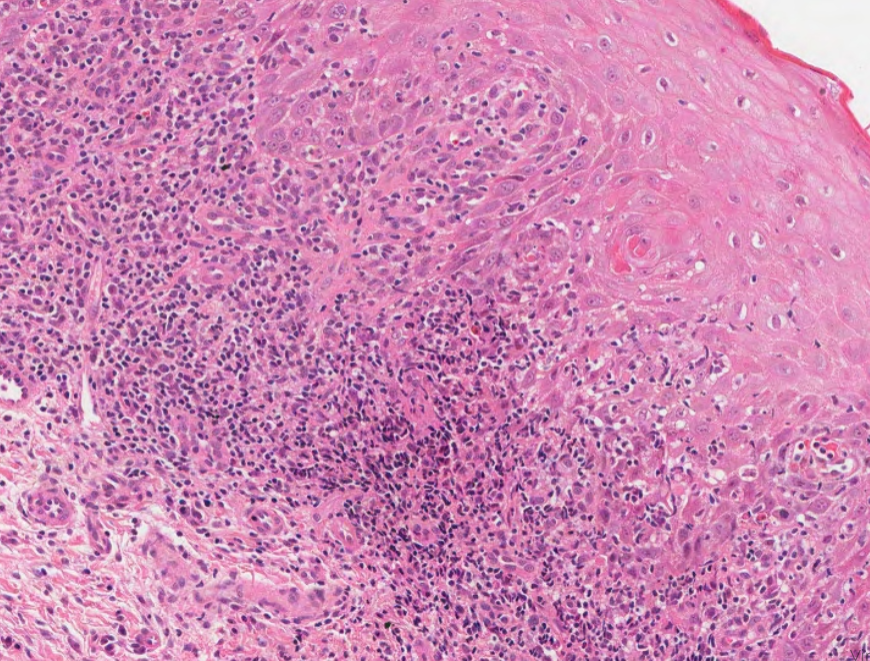

#caseoftheweek 🔬🔬🔬 What is causing a testicular lump in this patient with a raised LDH? View the full slide and thousands of others on the Leeds Virtual pathology website here:virtualpathology.leeds.ac.uk/slides/library… #pathX #PathTwitter #uropath